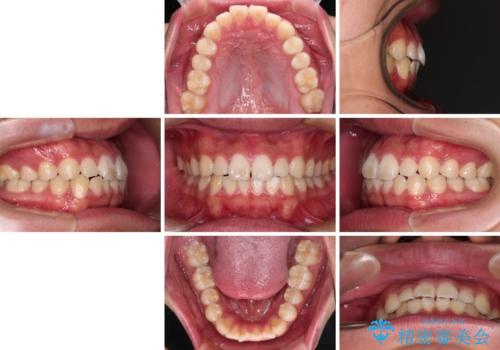

軽微叢生をインビザラインで 廉価版パッケージでの矯正治療

- 20代男性

- インビザライン・ライト

- 8ヶ月

- 2-5回

- 上下前歯の叢生を気にして来院された患者様です。

費用を抑え、期間もあまりかけずに治療をしたいとのことで、インビザライン・ライトを用いて矯正治療を行うこととしました。

- 治療費の目安: 50万円(税込)費用は治療当時の料金となります